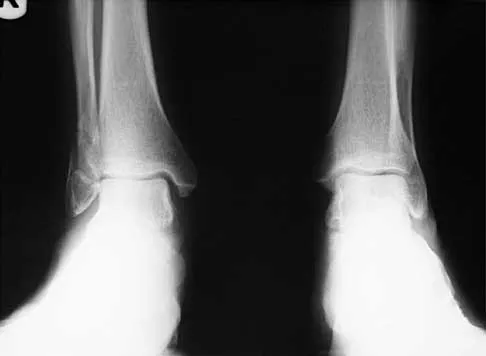

A 57-year-old man has had right ankle pain for the past 10 months following an injury that went untreated. Radiographs are shown in Figures 30a through 30c. Management should consist of

The radiographs reveal a malunited distal fibular fracture with shortening. Because there appears to be an adequate cartilage space within the ankle joint, the role of reconstruction would be to prevent arthrosis and the need for ankle arthrodesis, as well as to decrease symptoms. The treatment of choice is restoration of fibular length, alignment, and rotation with osteotomy plating, and bone grafting as needed. There is no indication for ligament reconstruction of a mechanically stable ankle, and tibial shortening osteotomy will not assist in correcting the deformity. Cast immobilization may assist with improvement of symptoms but will not correct the overall process. Determination of fibular length is best done by comparing the talocrural angle of the injured side with the uninjured side. The goal is to perfectly reduce the talus in the ankle mortise. Marti RK, Raaymakers EL, Nolte PA: Malunited ankle fractures: The late results of reconstruction. J Bone Joint Surg Br 1990;72:709-713. Geissler W, Tsao A, Hughes J: Fractures and injuries of the ankle, in Rockwood CA Jr, Green DP, Bucholz RW, Heckman JD (eds): Rockwood and Green's Fractures in Adults, ed 4. Philadelphia, PA, Lippincott-Raven, 1996, pp 2201-2206.